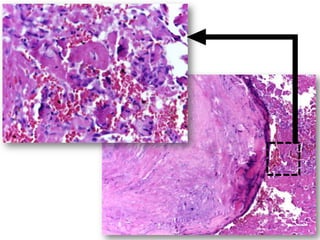

Uma mulher de 72 anos apresentou um nódulo assintomático na mucosa labial inferior há cerca de três meses. Após biópsia, o diagnóstico foi de flebólito, descartando as hipóteses iniciais de miofibroma ou neurofibroma.